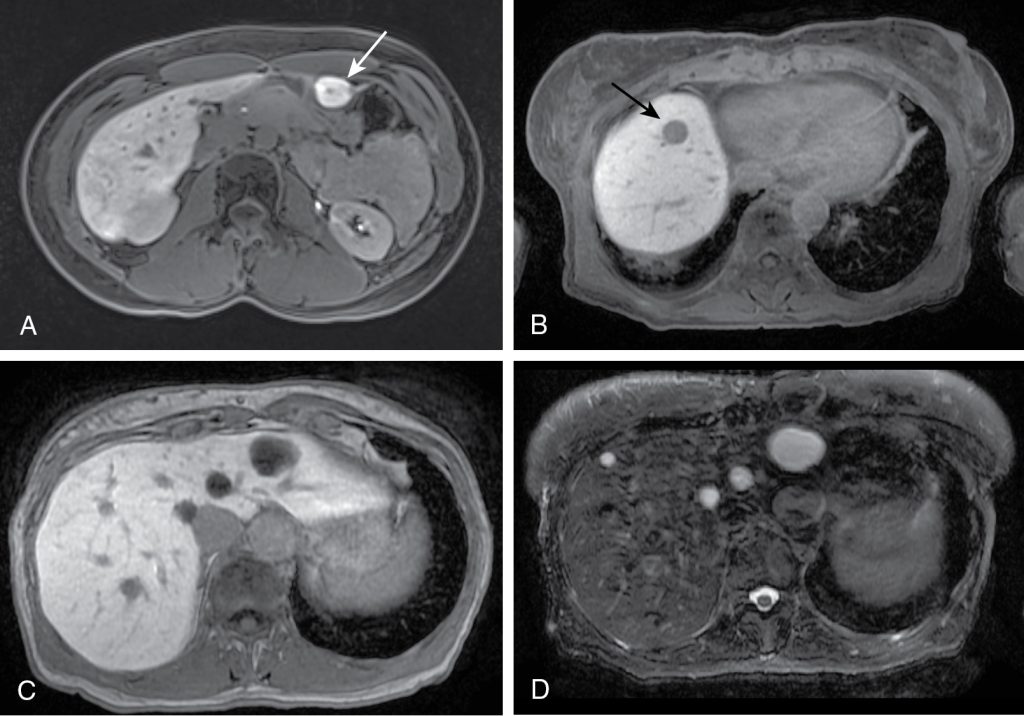

ضایعات بدخیم کبدی و مدیریت آنها: در میان ضایعات بدخیم کبد، کارسینوم هپاتوسلولار (HCC) شایعترین نوع سرطان اولیه کبد است که اغلب در بیماران مبتلا به سیروز یا عفونت مزمن ویروسی کبد دیده میشود. در تصویربرداری CT و